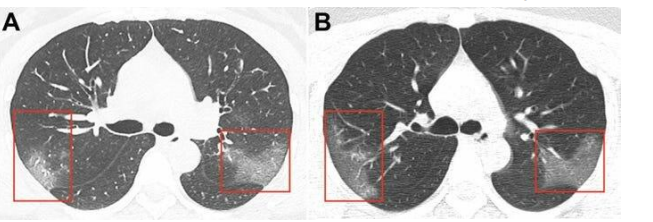

Doctors usually call lung damage "frosted" glass or consolidation.

This occurs due to the fact that the vessels and alveoli break the barrier and the alveoli of the lungs are filled with fluid from the vessels.

Not all the alveoli in the "frosted glass" zone are completely filled with liquid, but gas exchange is difficult, so it becomes difficult to breathe.

The diagnosis is made by a PCR smear from the nose, (if the material is found in the RNA of the coronavirus) + test for antibodies to Covid-19. Sometimes based on a typical picture of viral pneumonia in a chest CT scan. Changes in the lungs in viral pneumonia are poorly visible on a regular x-ray.

The radiological picture is usually characterized by a unilateral interstitial lesion in the form of pneumonitis, or bilateral focal drain pneumonia.

My Opinion of an Expert Clinical Pharmacist is that it is pneumonitis

Pneumonitis is an inflammation of the alveolar walls and interstitial lung tissue, in this case of infectious origin, which leads to scarring of the alveoli and fibrous changes in the supporting structures of the lungs.

The difference between pneumonitis and pneumonia is clearly visible on x-rays.

With pneumonitis, the pulmonary pattern is enhanced, darkening is observed in the lower part of the lungs, with pneumonia - darkening foci have uneven contours in various parts of the lungs.

Pneumonia is still an incorrect term, patients with COVID-19 develop virus-induced interstitiopathy (pneumonitis).

With pneumonitis, the pulmonary pattern is enhanced, darkening is observed in the lower part of the lungs, with pneumonia-darkening foci have uneven contours in various parts of the lungs.

Those changes that are detected in the lungs with covid are not true pneumonia. On a CT scan, the doctor sees a "frosted glass" - a decrease in the transparency of the lung tissue with a visible pattern of blood vessels and bronchi. This is due to a decrease in the airiness of the alveoli and thickening of the walls.

Two x-rays of the woman's chest.

The images show white spots in the lower corner of her lungs, which indicate what radiologists call «opaque frosted glass».

X-ray of the patient's chest. The difference between the images is 3 days.